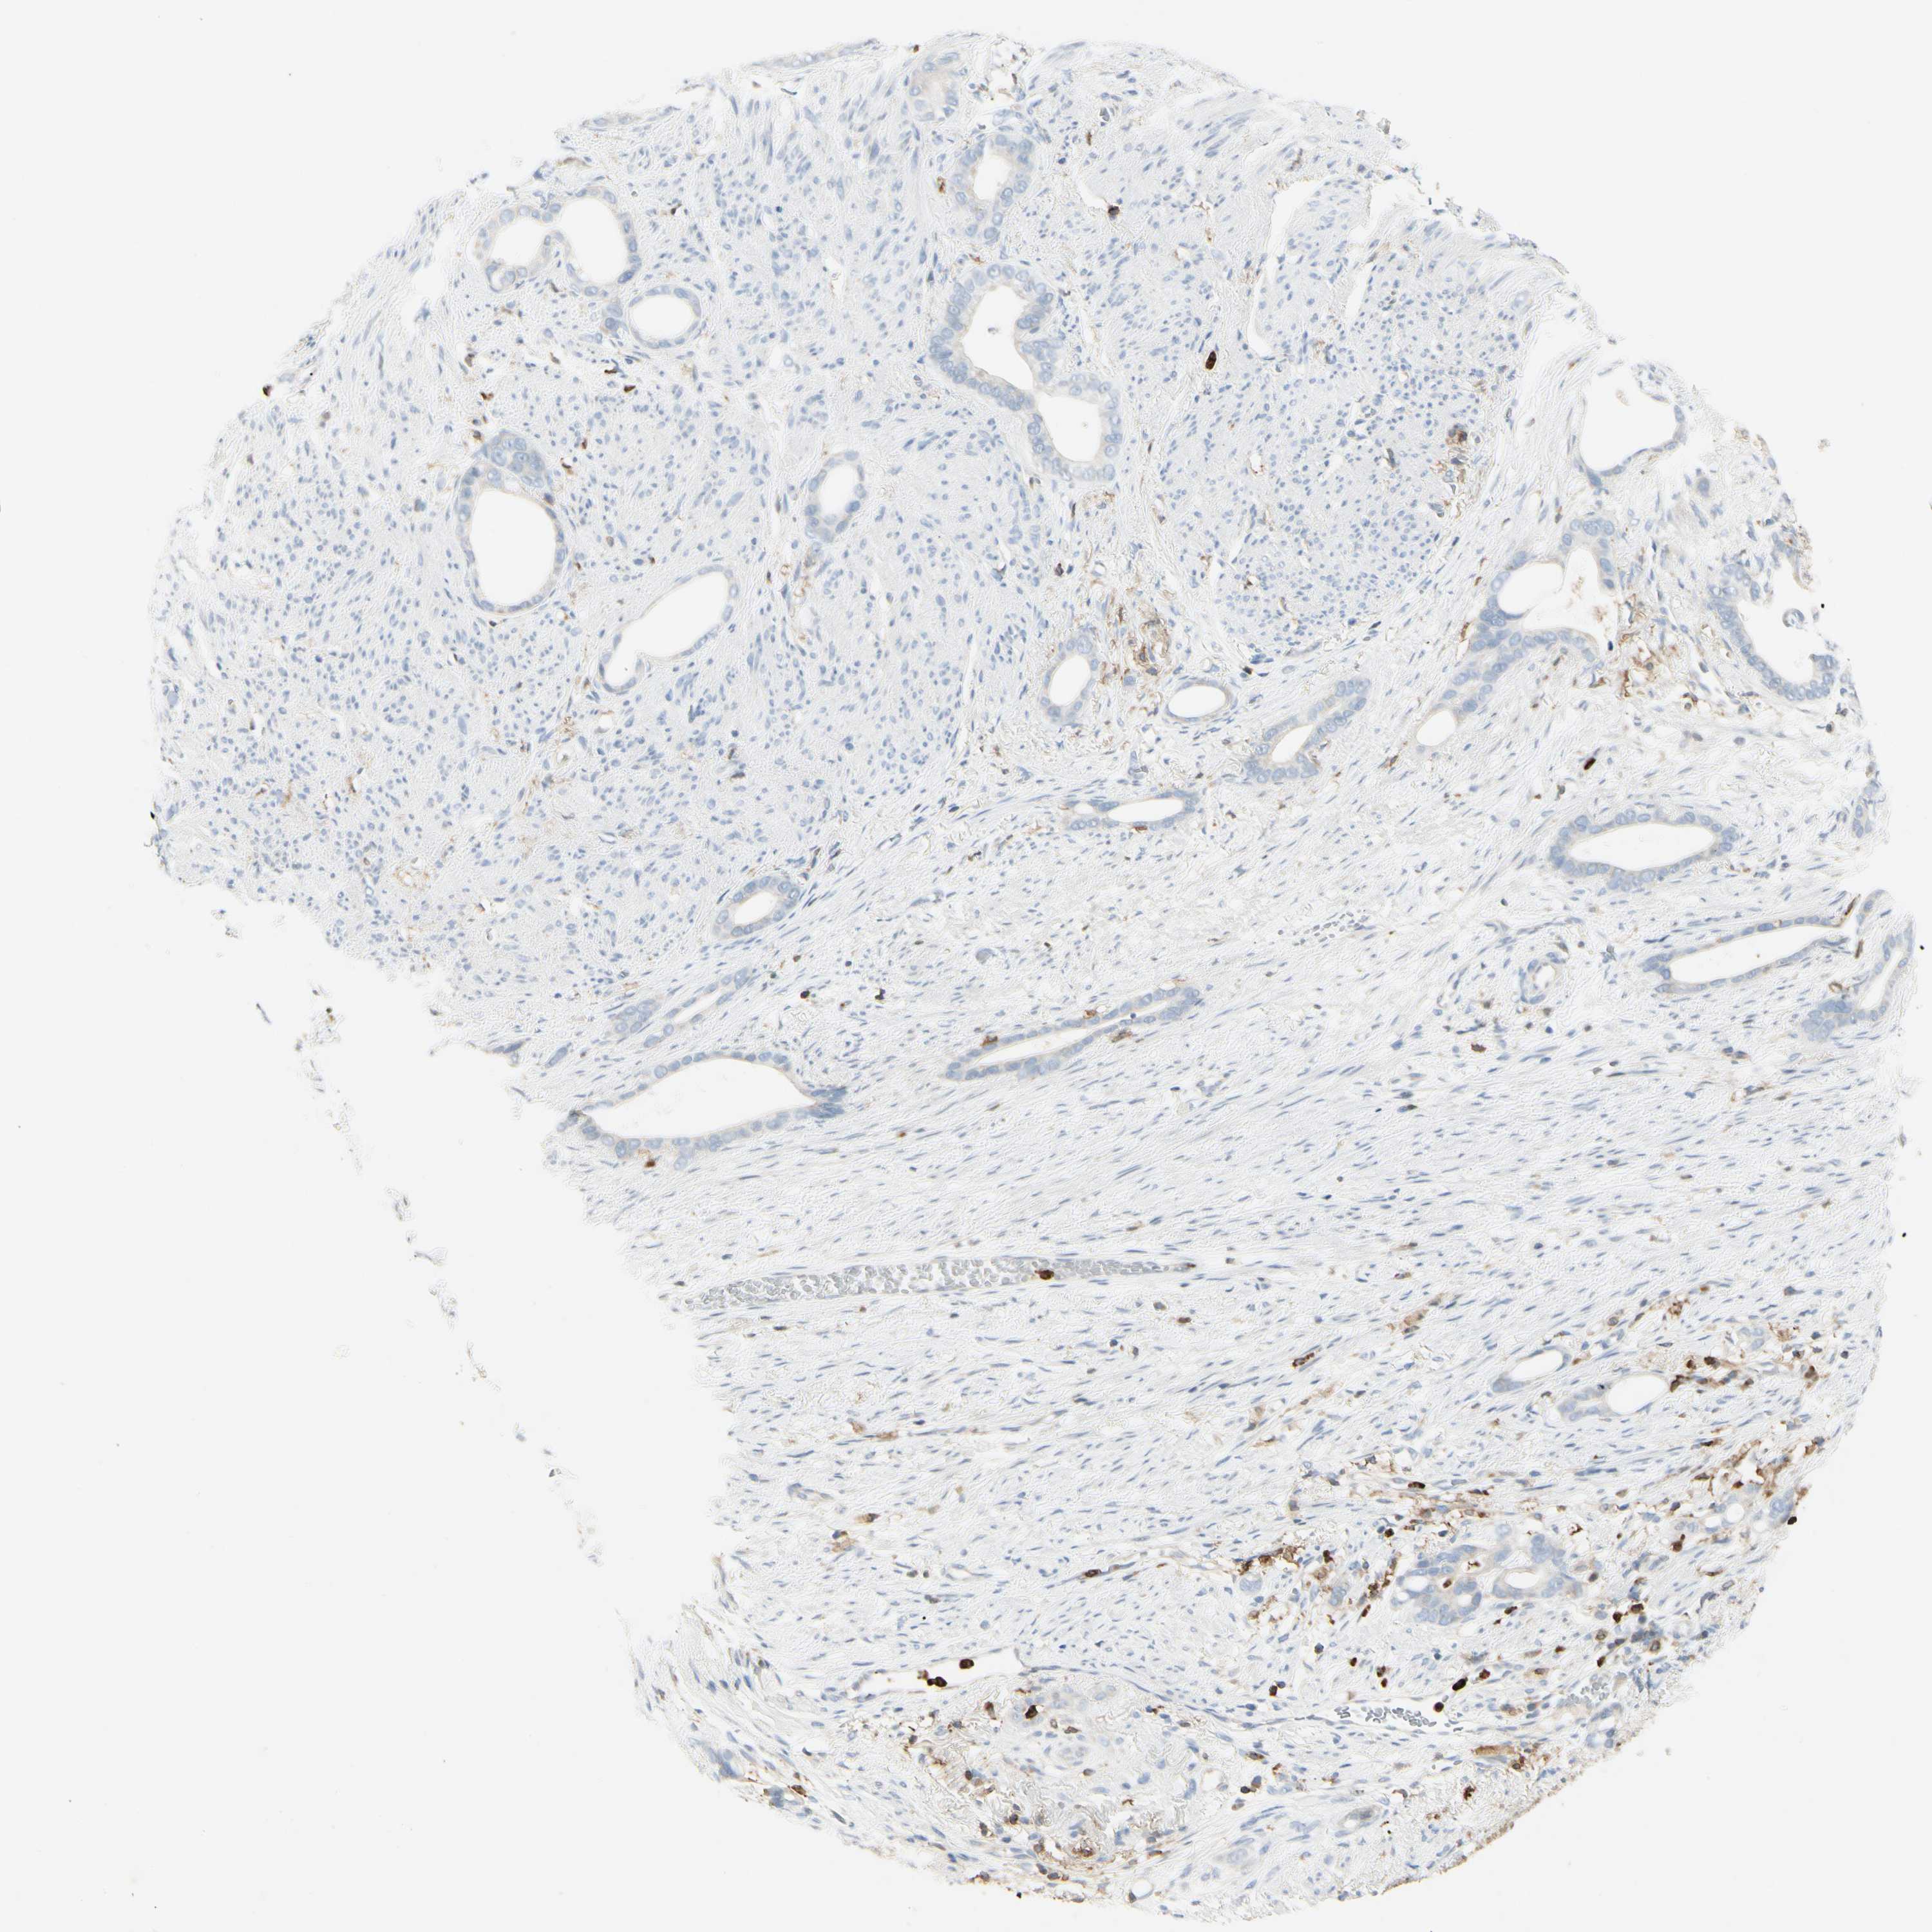

STOMACH CANCER - Protein expressioni

A mouse-over function shows sample information and annotation data. Click on an image to view it in a full screen mode. Samples can be filtered based on level of antibody staining by selecting one or several of the following categories: high, medium, low and not detected. The assay and annotation is described here.

Note that samples used for immunohistochemistry by the Human Protein Atlas do not correspond to samples in the TCGA dataset.

Antibody stainingi

Antibody staining in the annotated cell types in the current human tissue is reported as not detected, low, medium, or high, based on conventional immunohistochemistry profiling in selected tissues. This score is based on the combination of the staining intensity and fraction of stained cells.

Each image is clickable and will lead to virtual microscopy that enables deeper exploration of all samples and also displays staining intensity scores, fraction scores and subcellular localization as well as patient and tissue information for each sample.

Antibody HPA008877

Antibody HPA016894

Staining

High

Medium

Low

Not detected

Intensity

Strong

Moderate

Weak

Negative

Quantity

>75%

75%-25%

<25%

None

Location

Nuclear

Cytoplasmic/membranous

Cytoplasmic/membranous,nuclear

Adenocarcinoma, NOS